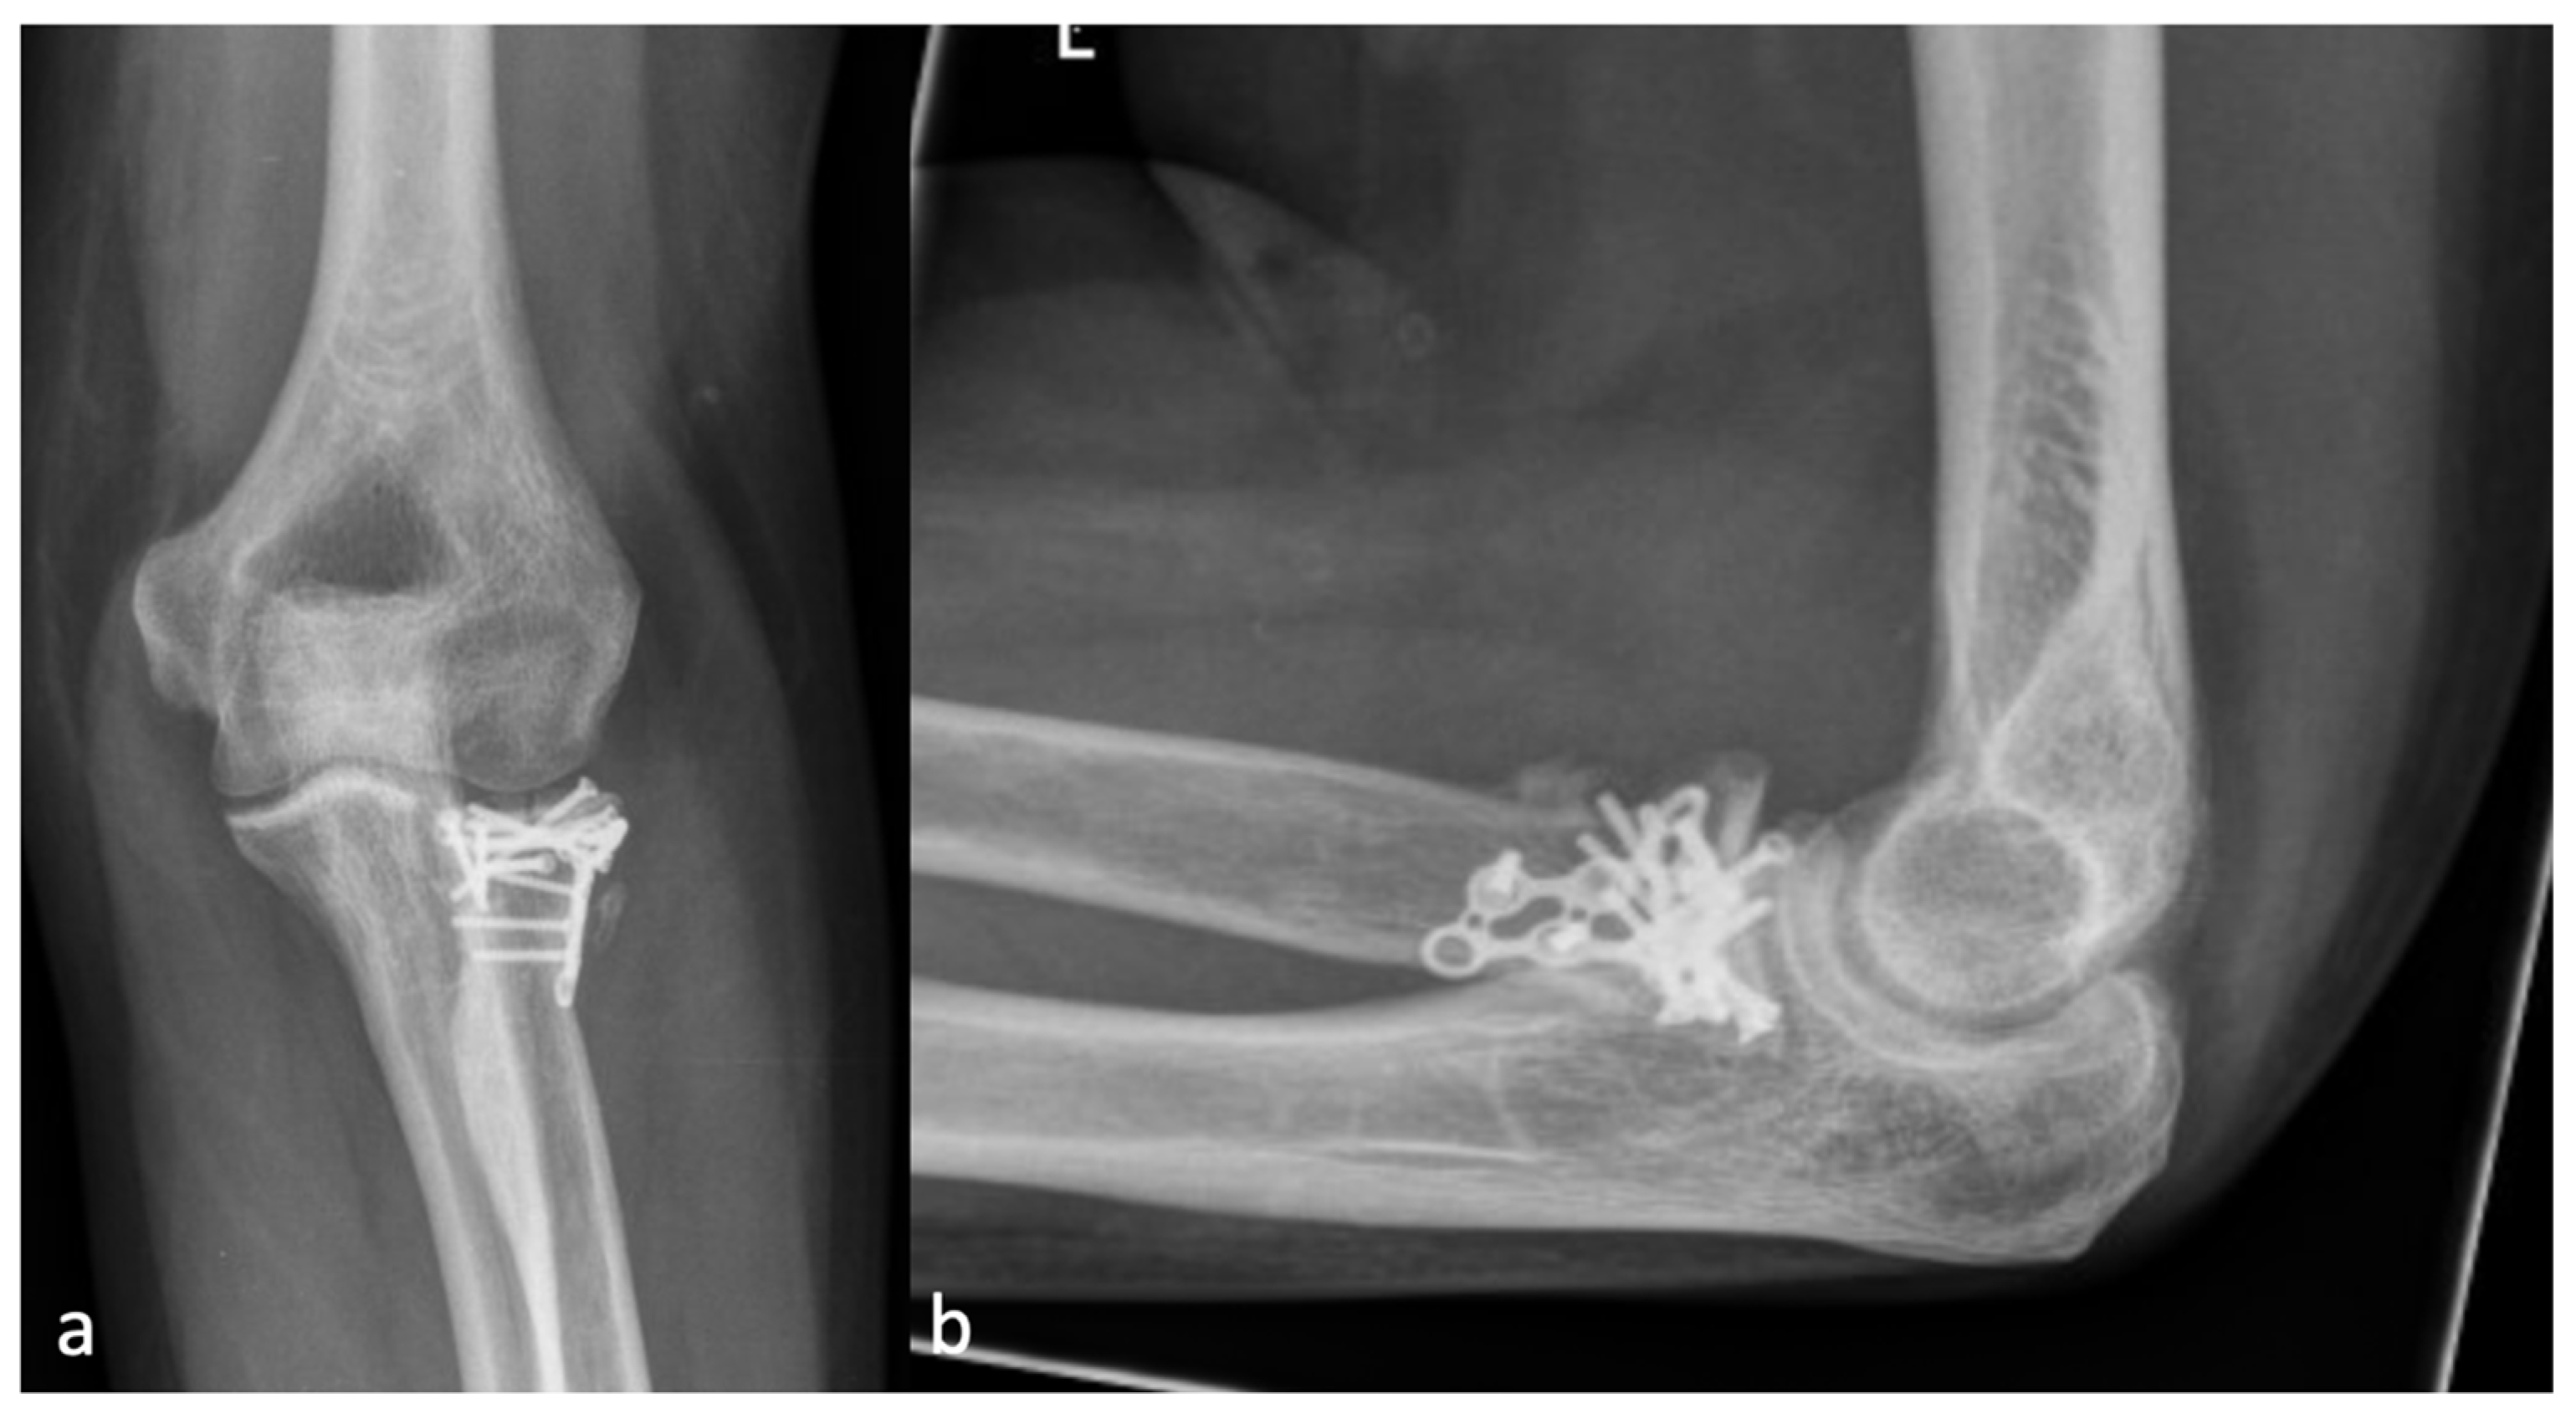

Figure 2.

(a) The AP and (b) the lateral X-ray with a radial HO smaller than the diameter of the radial head, which represents an HO 1 r.